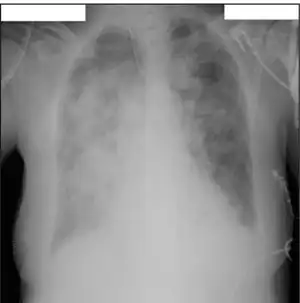

Influenza B virus particles , isolated from a sample and then propagated in cell culture